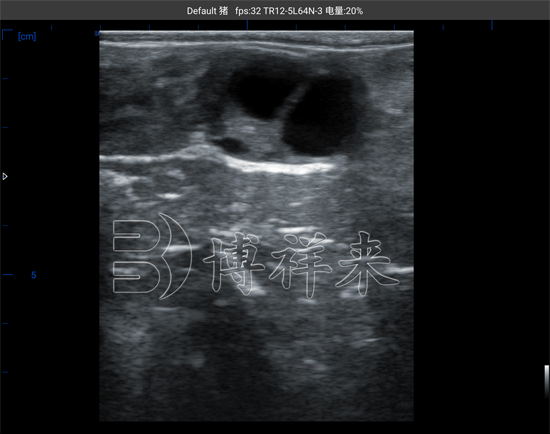

在B超影像下,母牛卵巢上的卵泡、黄体、甚至卵巢囊肿都能被清晰地识别。正常卵泡在图像上呈圆形或椭圆形的黑色无回声区,周围有一圈均匀的高回声边界,这意味着卵泡内部充满液体。随着发情周期推进,卵泡逐渐增大,从***初的2毫米左右发育到7毫米以上,接近排卵期时壁变薄、形态略不规则,这是排卵即将发生的信号。

在母牛的繁殖周期中,卵泡与黄体的变化交替出现。排卵后,卵泡塌陷并形成黄体,B超影像表现为回声增强、结构较实的圆形组织。通过观察黄体的存在与血流情况,技术人员不仅能确认排卵是否发生,还能在配种后21天左右通过多普勒功能检测黄体血流强度,辅助判断母牛是否已经怀孕。